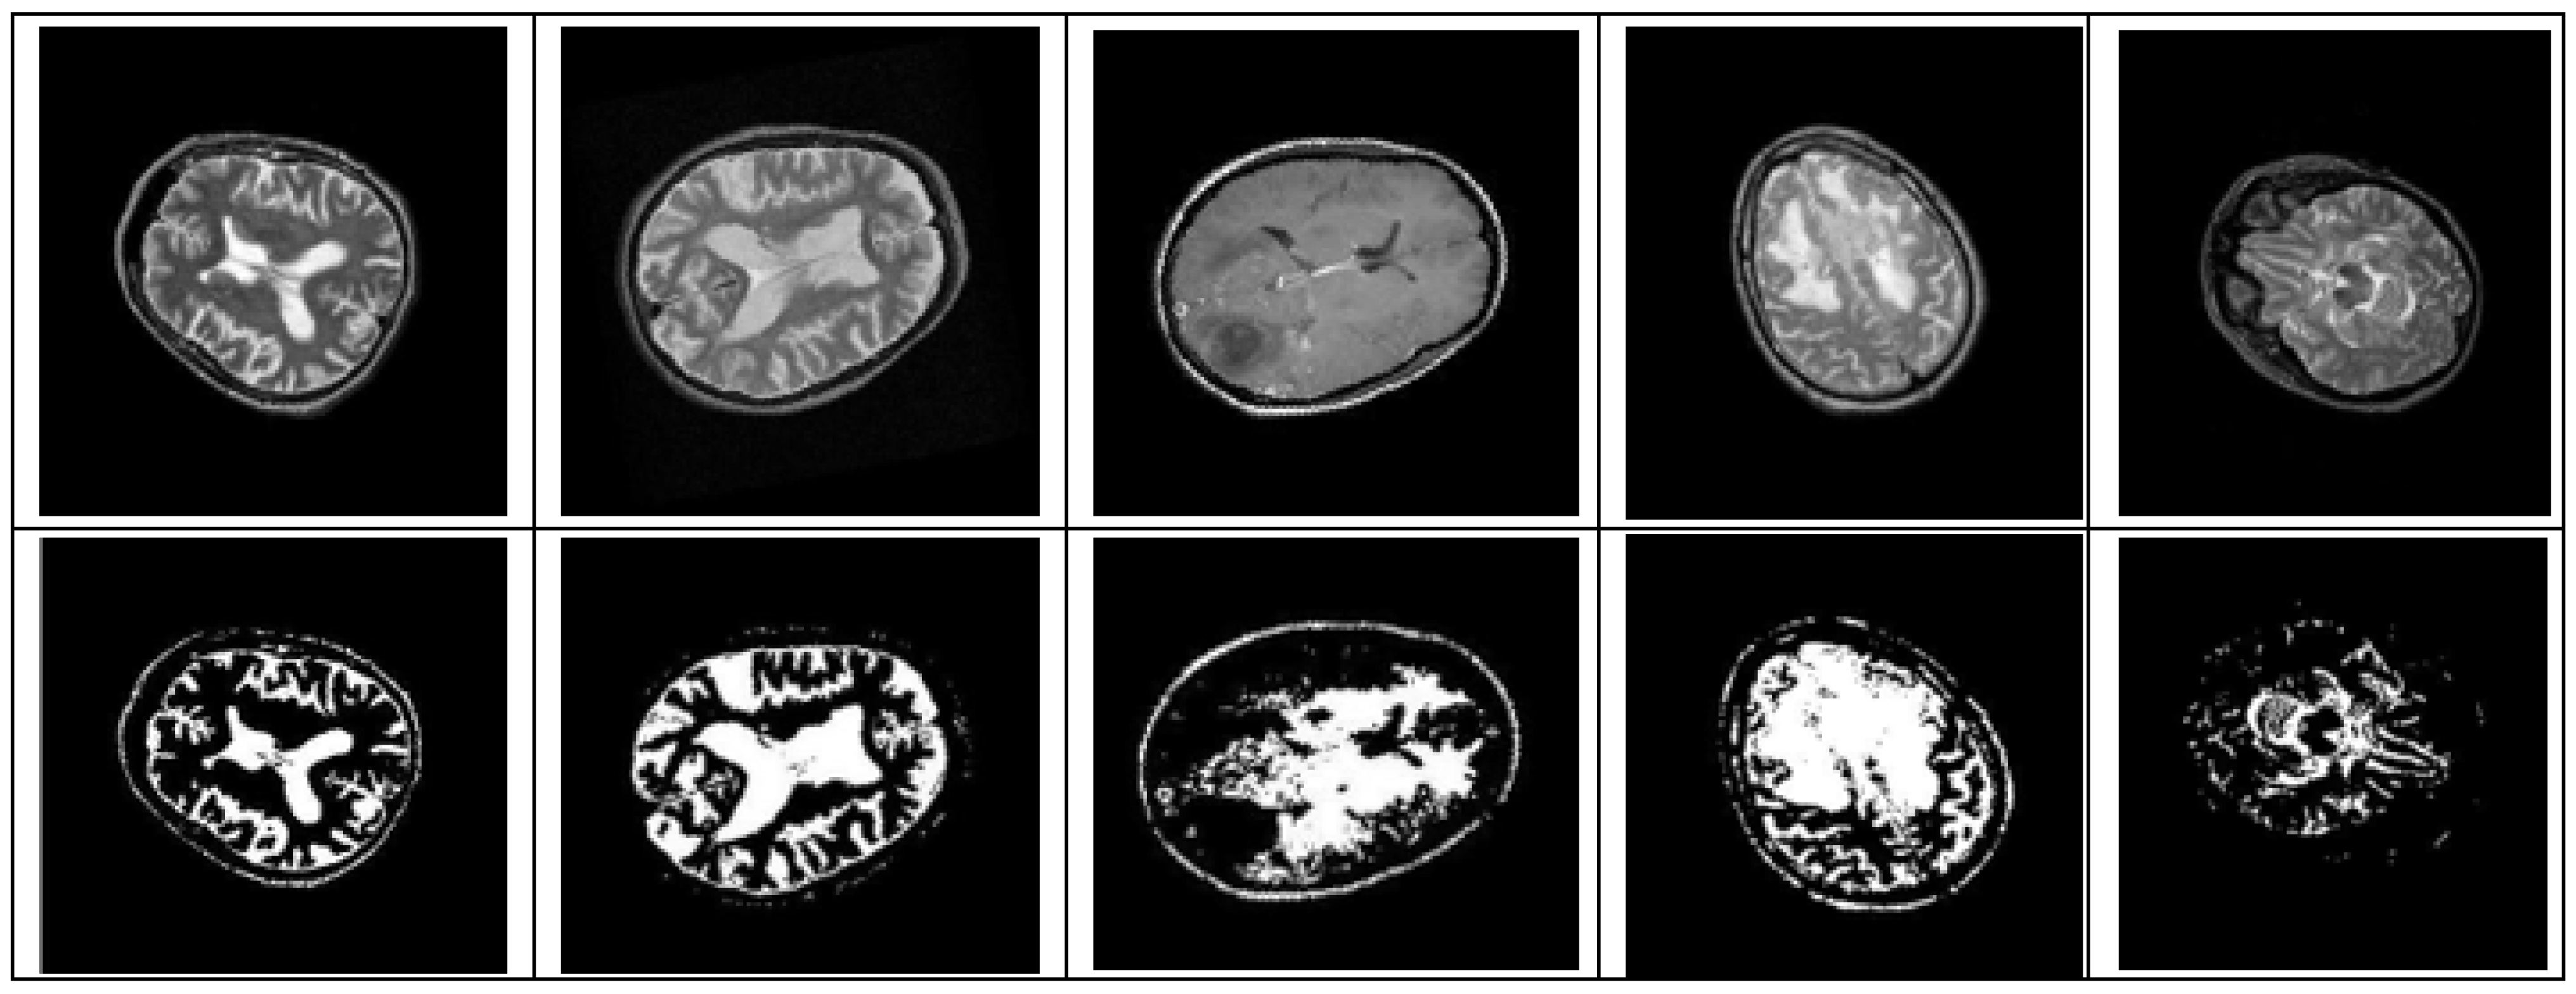

3.1. Pre-Processing

3.2. Segmentation

4.3. Simulation and Observation/Output of Simulation

5.1. Result 1: Experiment with Distorted/Simulated MRI Image Dataset

- (a)

- Abnormality Classification for Distorted/Simulated MRI Image:

- (b)

- Tumor Classification for Distorted/Simulated MRI Image